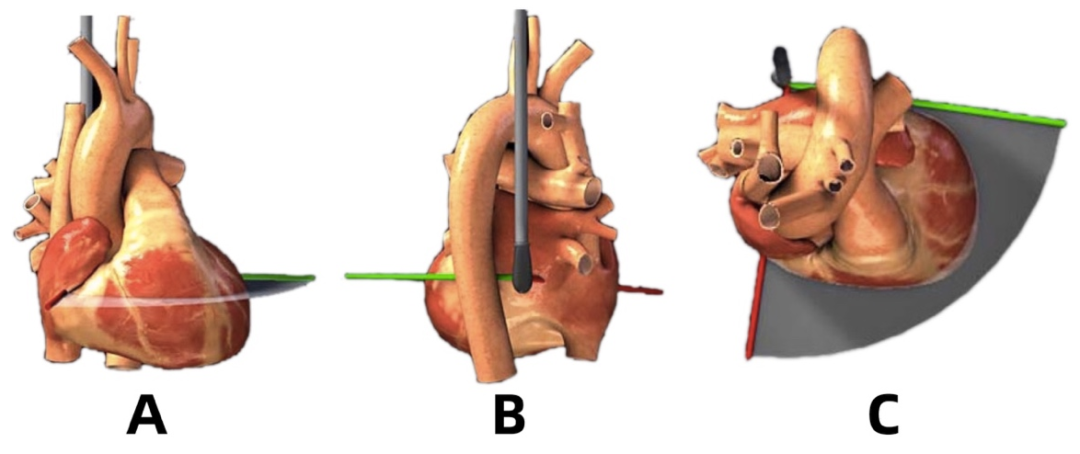

食管中段左室长轴切面(LAX view)

超声探头位置与前述两腔心切面时一致、位于左心房后部,旋转晶片角度至 130° 左右(图 14)。可在长轴方向显示主动脉瓣和左室流出道,调整超声探头深度使得整个左心室在图像中显示。左心室前间膈和下侧壁、二尖瓣 A2 及 P2 均能清晰显示(图 15)。

该切面用于诊断二尖瓣、主动脉瓣、主动脉根部和室间隔病变,也可用于评估左室功能。此切面也是二尖瓣缘对缘修复术(TEER)中的重要参考依据。

另有两个基本切面与左室长轴切面存在联系:即左室流出道切面(LVOT view)以及主动脉瓣长轴切面(AV LAX view)。

前者与左室长轴切面基本相同。而后者相较于左室长轴切面,超声探查深度更浅,图像关注点主要在于流出道及主动脉根部,左室及二尖瓣仅显示部分(图 16)。